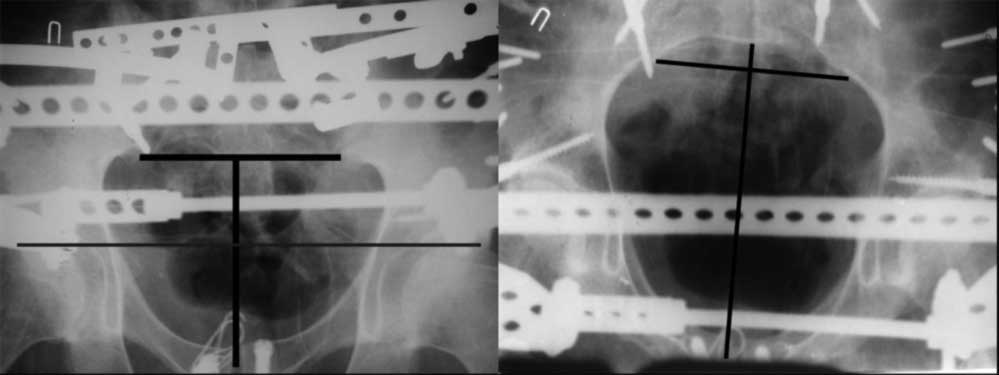

закрытое низведение правой половины таза кольцевым аппаратом (с фиксацией задних отделов), затем проведение илиосакральных винтов, реостеосинтез лонного сочленнения, дальнейшая фиксация в аппрате 2-3 мес. Похожий пример в приложении.